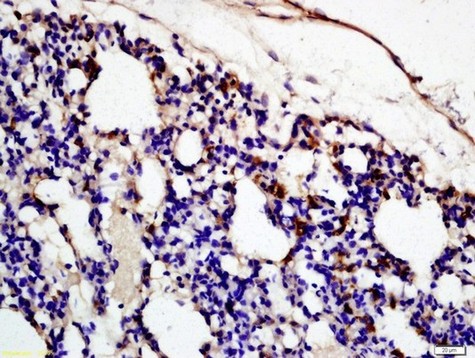

Immune complexes can activate the complement system through the classical and alternative pathways, leading to allergic reactions and causing damage to glomerular tissue. In glomerular diseases, complement is primarily activated through the alternative pathway, with a minority activated through the classical pathway. Commonly used complement antibodies in kidney biopsies include C3, C4, and C1q. C3 is a central complement component in the human complement system. It reacts with and deposits in glomeruli during renal biopsies, characteristically depositing on the walls of capillaries outside the glomeruli. C3 is expressed in glomerulonephritis and otosclerosis. It is primarily used for detecting the types of immune complexes in glomerulonephritis, aiding in the classification of the condition.

Complement C3c antibody reagents can specifically bind to the complement C3c molecular antigen. Immunohistochemistry kits containing complement C3c antibody reagents are suitable for the auxiliary diagnosis of glomerular diseases (such as membranoproliferative glomerulonephritis, lupus nephritis) and autoimmune diseases (such as SLE).